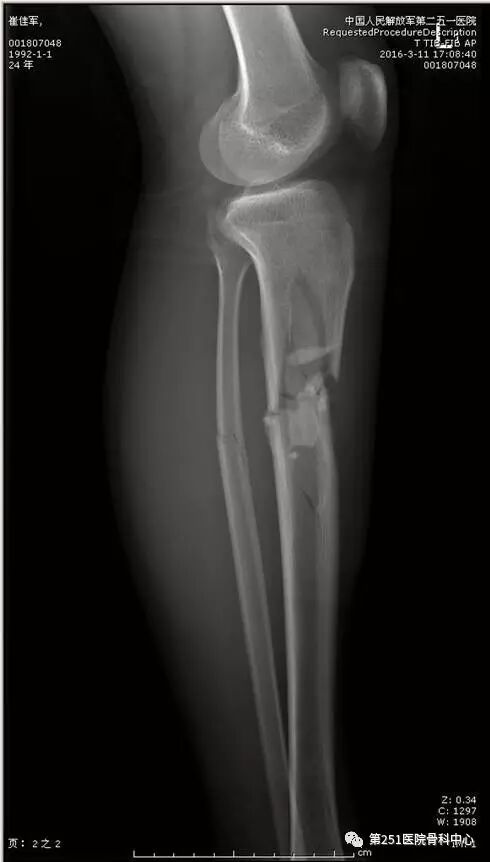

病例8:男性,24岁,车祸伤,胫腓骨近段粉碎性骨折。

![]()